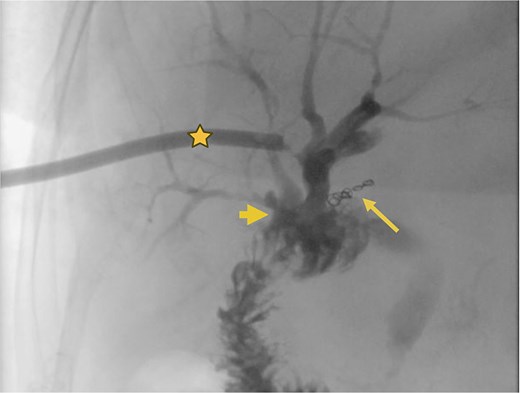

Transcatheter arterial embolization of the right hepatic artery. (a) Selective transcatheter arterial embolization (TAE) of the branch of the right hepatic artery (Segment V) (arrow). (b) Post-embolization image of the pseudoaneurysm in the branch (Segment V) of the right hepatic artery with microcoils (arrow), showing no contrast medium leakage. Right percutaneous catheter (star).

Supranastomotic percutaneous transcatheter cholangiography. Hepaticojejunostomy (arrowhead), microcoils (arrow), and percutaneous catheter (star).